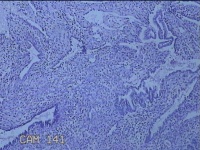

宫腔内容物

性别

女

年龄

47岁

临床诊断

1.异常子宫出血 2.慢性宫颈炎

一般病史

不规则阴道流血21天。

标本名称

大体所见

灰白暗红色不规则碎组织2.5x1.8x0.3cm一堆。

图4